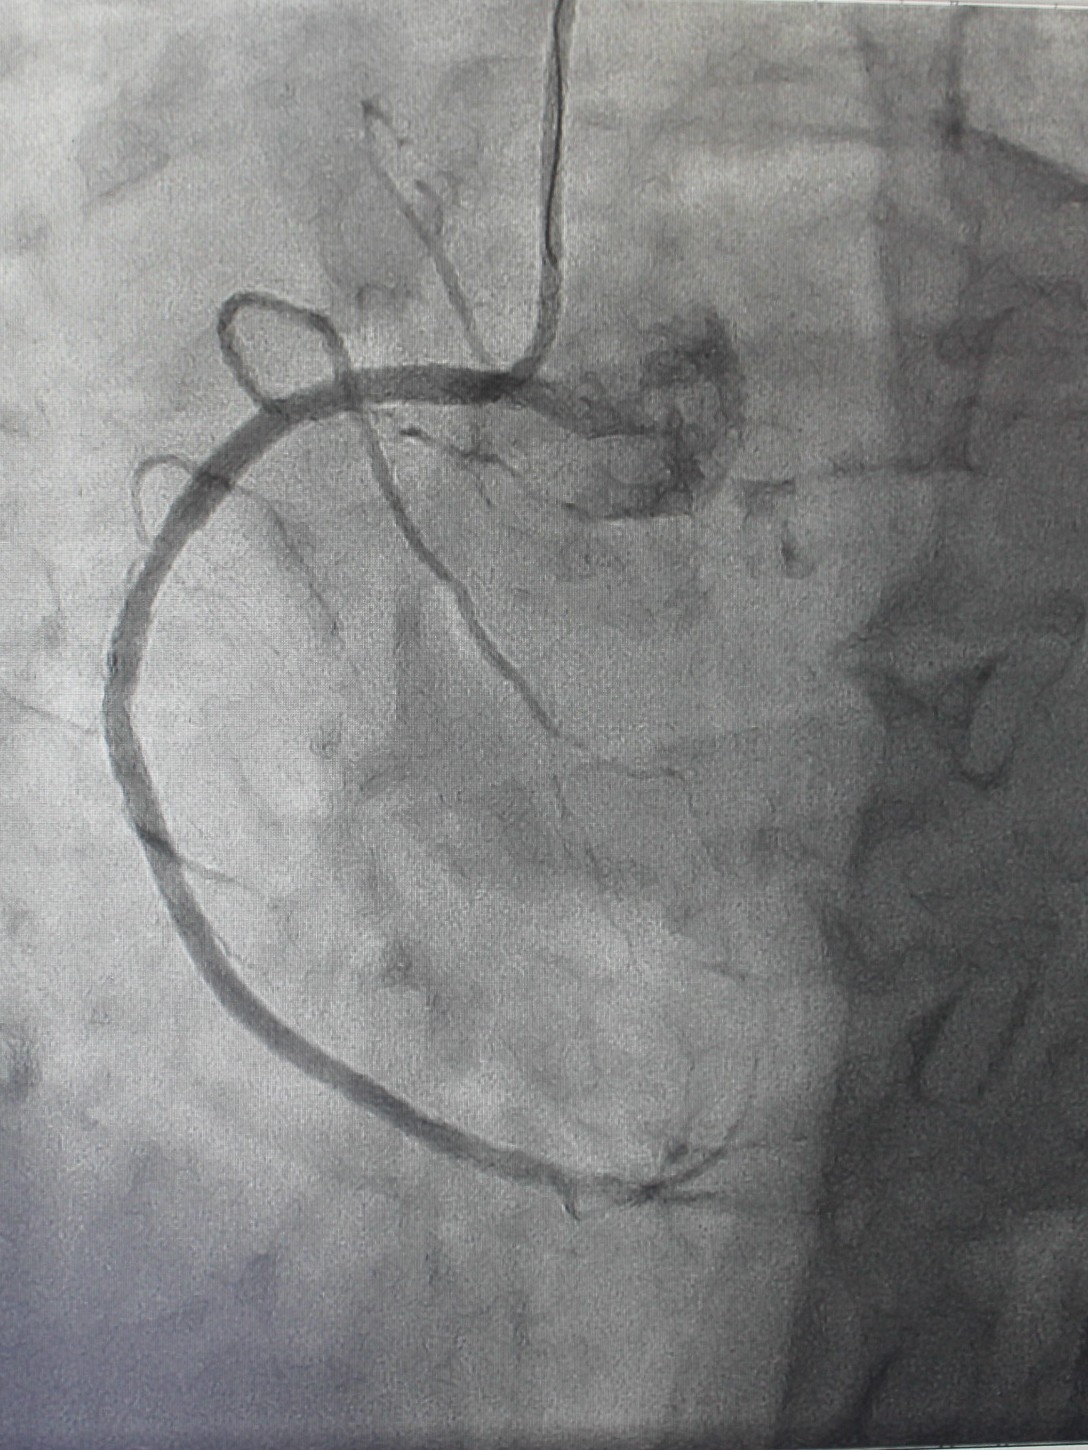

По экстренным показаниям проведена коронароангиография, выявлено стенозирующее многососудистое поражение: стеноз (сужение) передней межжелудочковой ветви левой коронарной артерии 80% в проксимальной трети, стеноз огибающей ветви 75% в дистальной трети (при том, что существенным рассматривают сужение артерии > 50%), тромботическая окклюзия правой коронарной артерии (в проксимальной трети). Рентгенхирурги выполнили тромбэкстракцию из правой коронарной артерии, баллонную ангиопластику со стентированием правой коронарной артерии (2 стента с лекарственным покрытием). Операция продолжалась около часа, после чего пациент продолжил лечение под наблюдением врачей отделения кардиореанимации; через двое суток был переведен в отделение кардиологии для дальнейшего лечения.

| Окклюзия правой коронарной артерии, кровоток отсутствует | Аспирационным катетером выполнена механическая тромбэкстракция |

| Обнаружены участки стенозирования артерии | Установлены 2 стента, стенты раскрыты | На контрольной ангиограмме: коронарный кровоток восстановлен, раскрытие стентов полное, позиционирование адекватное |